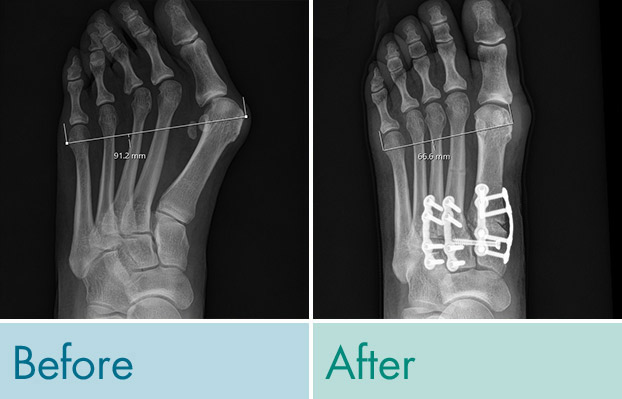

‘Metatarsus Adductus’ (MTA) deformity of the foot affects approximately 30-35% of patients with symptomatic hallux valgus; also known as bunions. This compound pathology increases the risk for deformity recurrence in 30% of cases if not managed properly from a surgical perspective. Patients that have this foot deformity are born with the problem and it does not spontaneously resolve with age or growth. The deformity becomes rigid and fixed as patients reach skeletal maturity. The long bones of the foot called the metatarsals are all deviated toward the midline of the body.

Patients with MTA appear to have severe bunions with a deviation and painful crowding of the great toe and lesser toes. Fitting shoes can also be very difficult due to a mismatch in foot width. Patients tend to have a very wide forefoot and a narrow hindfoot. The prominence of the big toe joint becomes impinged when wearing shoes. This creates a source of frequent irritation and pain that can ultimately result in nerve injury, limitation in motion, and joint arthritis.

The systematic approach to the surgical correction of combined hallux valgus and metatarsus adductus deformities provides the benefit of a standard reproducible surgical approach that achieves tri-planar correction at multiple joints to fully correct the compound deformity. This technique supports early weight bearing for mild, moderate and severe deformities.

This surgical technique was first described and published in the Journal of Foot and Ankle Surgery by Dr. JP McAleer and his co-authors. It makes use of specialized instrumentation he and his colleagues specifically designed to cut, manipulate and reduce the lesser tarsal metatarsal joint deformities prior to addressing the bunion via Lapiplasty® 3D Bunion Correction. This technique provides patients the benefits of a reproducible approach that facilitates the use of locking plate technology to maintain the correction at multiple levels. In our experience patients have a narrowing of the forefoot which improves foot proportions and may improve shoe wear and comfort.